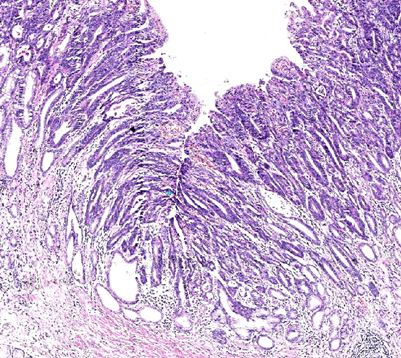

重度异型增生(又称为高级别上皮内瘤变)